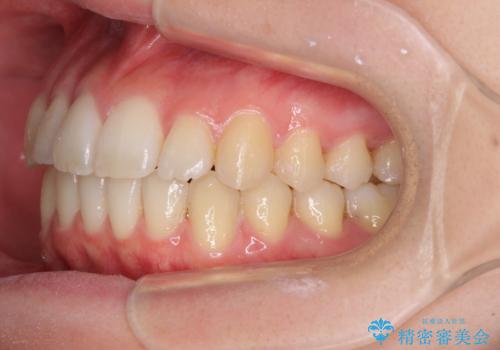

気になる前歯を整えたい インビザライン・ライトでの矯正治療

- ちょっとしたデコボコを整えたいとのことで来院された患者様です。

歯列不正は軽微であったため、インビザライン・ライトにより、費用を抑えて矯正治療を行うこととしました。

上下前歯の捻れが改善され、患者様には大変満足していただきました。